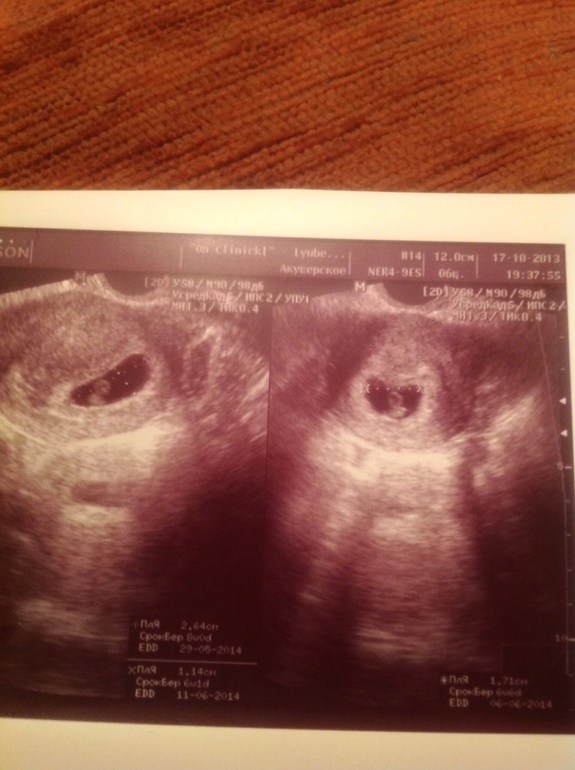

Результаты: УЗИ, КТГ, доплера, скринингаИтак, вот наше первое фото !!!! Нам 6,5 неделек ( акушерских)!!!! Видела сегодня как бьется наше сердечко !!!! Я счастлива !!!!!

Итак, вот наше первое фото !!!! Нам 6,5 неделек ( акушерских)!!!! Видела сегодня как бьется наше сердечко !!!! Я счастлива !!!!!